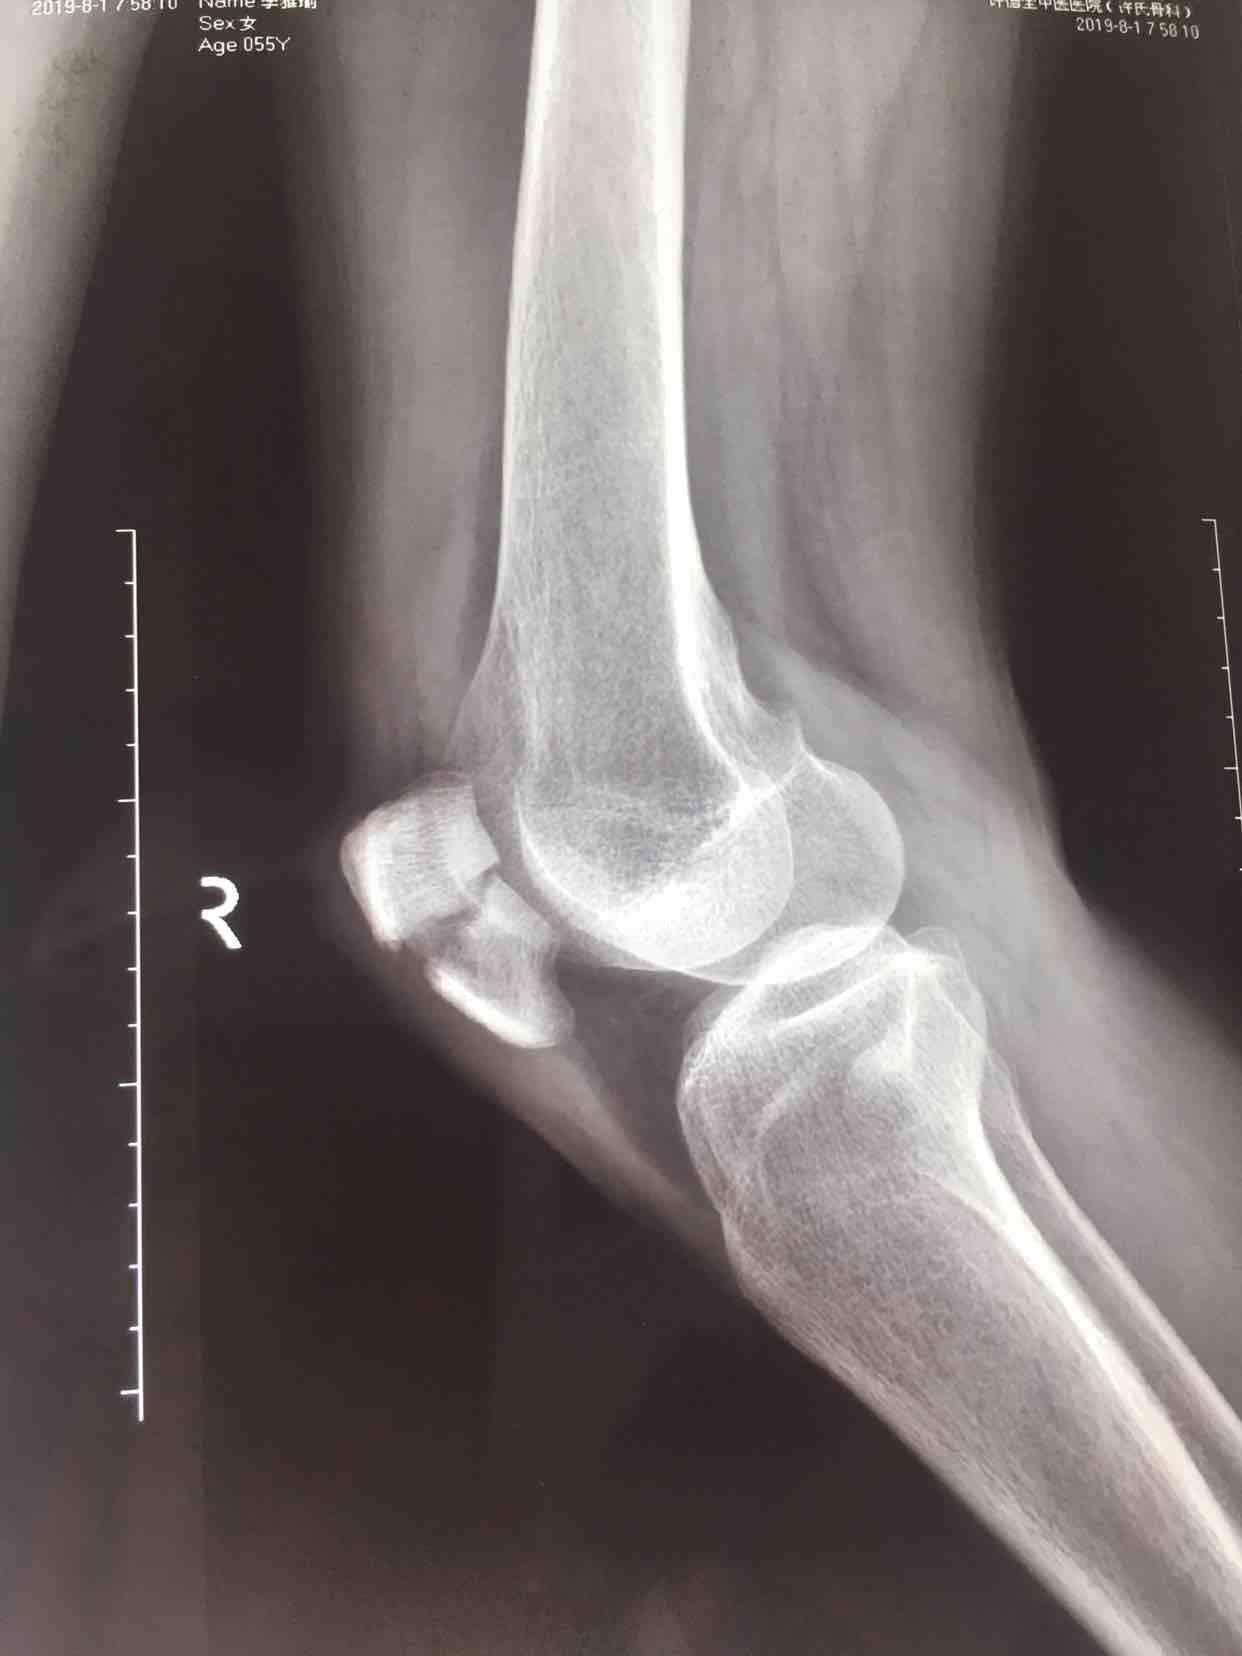

髌骨骨折(髌骨爪➕克氏针应用)

骨折 髌骨骨折

摔伤后右膝部肿痛,活动受限1小时入院。既往身体健康,无特殊不良嗜好。

生命体征平稳,心肺复未见异常。右膝部肿胀明显,皮色微红,皮温高,可及骨檫音及骨折断端,压痛明显,伸膝关节受限,末梢血运感觉正常。

诊断右髌骨骨折在腰麻下行切复内固定术,术后抗炎,消肿等处理。